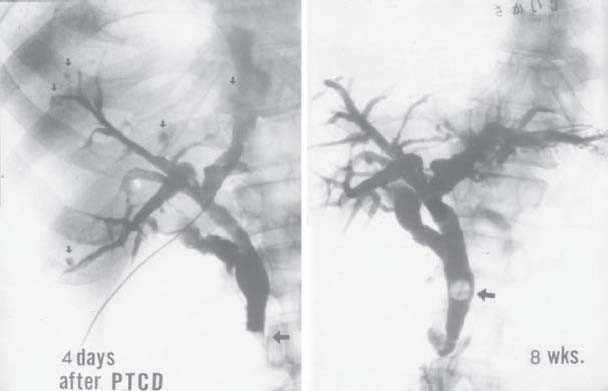

Fig. 4

figure 4

Cholangiogram 4 days later, when the condition of the whole body had been improved. The numerous cyst-like shadows in disorderly shapes continuing from the hepatic bile duct that were seen in the first instance of cholangiography were much fewer and much smaller in size (left). Cholangiography at the time when the whole body condition had been completely improved shows that the cyst-like shadows in the liver had completely disappeared and there was only one spot of suspended stones in the common bile duct